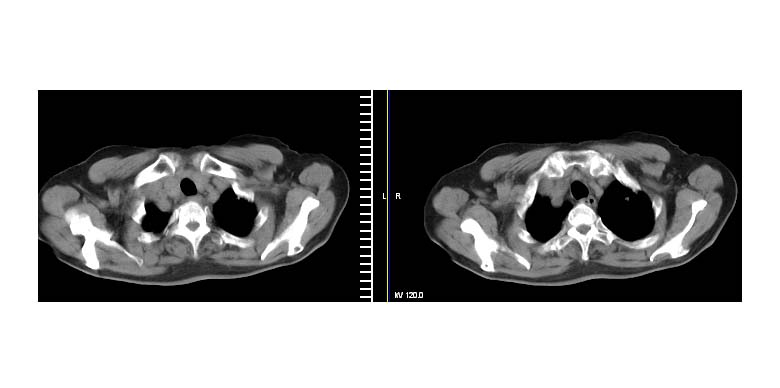

左上肺周围型肺癌伴纵隔淋巴结转移

考虑左上肺周围型肺癌伴纵隔淋巴结转移。

左上肺软组织肿块,有分叶,短毛刺,气管旁间隙见有肿大淋巴结,考虑左上周围型肺癌伴纵隔淋巴结转移。

左上肺周围型肺癌伴纵隔淋巴结转移。

考虑左上肺周围型肺癌伴纵隔淋巴结转移

左肺上叶前段肺癌并纵隔淋巴结肿大。

左上肺癌并纵隔淋巴结转移!